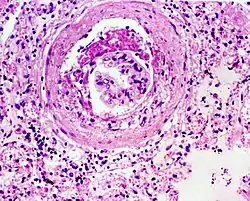

Glomerulosclerosis is the hardening of the glomeruli in the kidney. It is a general term to describe scarring of the kidneys' tiny blood vessels, the glomeruli, the functional units in the kidney that filter urea from the blood.

Proteinuria (large amounts of protein in the urine) is one of the signs of glomerulosclerosis. Scarring disturbs the filtering process of the kidneys and allows protein to leak from the blood into the urine. However, glomerulosclerosis is one of many causes of proteinuria. A kidney biopsy (the removal of a tiny part of the kidney with a needle) may be necessary to determine whether a patient has glomerulosclerosis or another kidney problem. About 15 percent of people with proteinuria turn out to have glomerulosclerosis.

Both children and adults can develop glomerulosclerosis, which can result in different types of kidney conditions. One frequently encountered type of glomerulosclerosis is caused by diabetes. Drug use or infections may cause focal segmental glomerulosclerosis (FSGS), a very chronic kidney condition. FSGS may also occur in patients with AIDS, but most cases are of unknown cause.